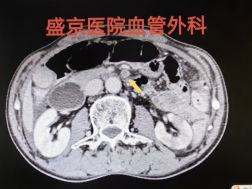

★ 案例八

57岁,女性,主诉:腹痛5天,加重2天,急诊诊断为急性肠系膜静脉血栓形成、急性腹膜炎, WBC30000/ml以上,他院介入科行经皮门静脉肝静脉穿刺吸栓术后,仍然感染性休克。

对于急性肠系膜缺血伴有腹膜炎的患者,迅速开腹探查、切除感染坏死肠管是关键!!!